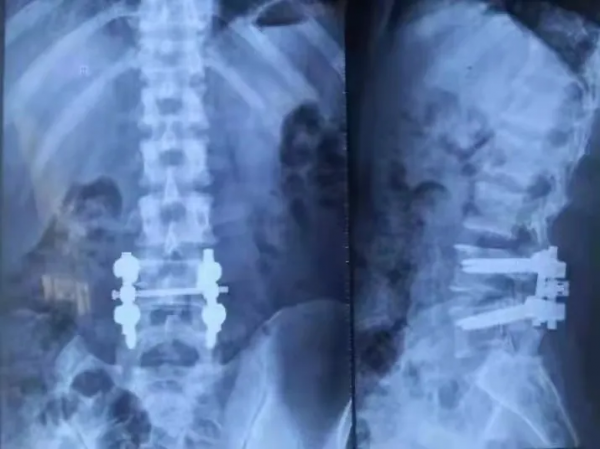

手術後第二天病人的腰痛及下肢放射痛即獲得明顯緩解,複查X線片,腰椎固定可靠,顯示手術完美。術後第5天病人已經可以佩戴護腰下床活動,術後一週就自己走出病房、順利出院了。